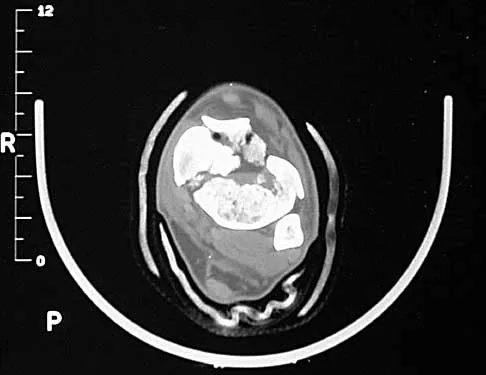

A 32-year-old man sustained a closed injury after falling 25 feet from a roof. His ankle and foot are severely swollen. Radiographs and CT scans are shown in Figures 29a through 29d. Initial management should consist of